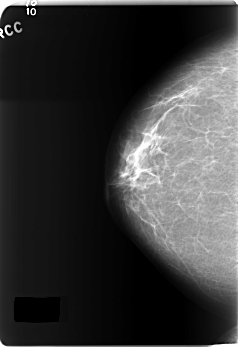

C_0163_1.RIGHT_CC

RIGHT_CC LINES 5896 PIXELS_PER_LINE 4032 BITS_PER_PIXEL 12 RESOLUTION 50 NON_OVERLAY